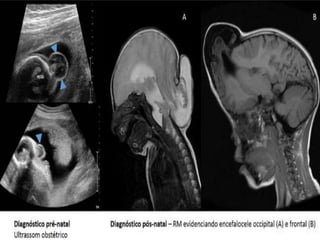

*Encefalocele

Es una protrusión o un

bulto (en forma de saco)

formado por la salida del

encéfalo y las membranas

que lo recubren a través

de una abertura en el

cráneo.

Clasificación Anteriores

Posteriores

Diagnostico

Prenatal

Ecografía

Alfa-proteínas maternas

Posnatal

Parto por cesaría

TC

RM